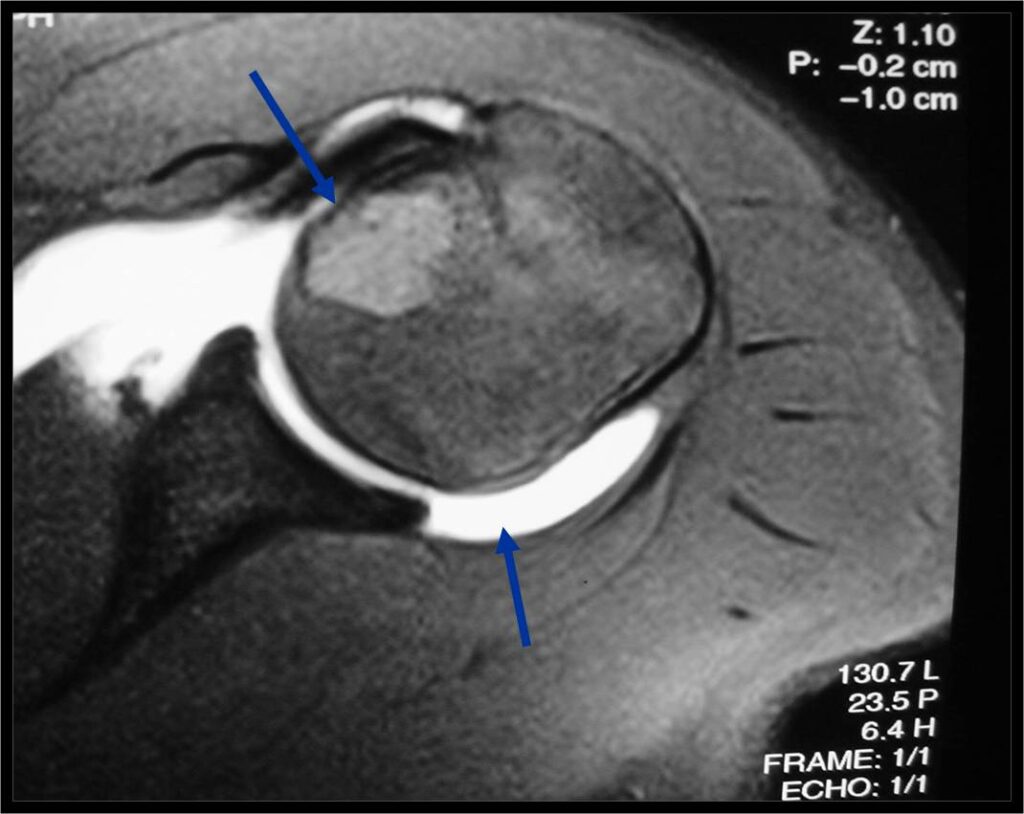

Treatment of a Chondroblastoma of Proximal Humerus with Intralesional Curettage Resection, Cryosurgery and Bone Grafting

- intralesional curettage resection and bone grafting most common treatment

- Cement and internal fixation may also be used to fill the defect after removal for selected patients

- High risk of local recurrence after curettage alone

- Local adjuvants such as cryosurgery (liquid nitrogen application) may be considered to decrease the risk of local recurrence